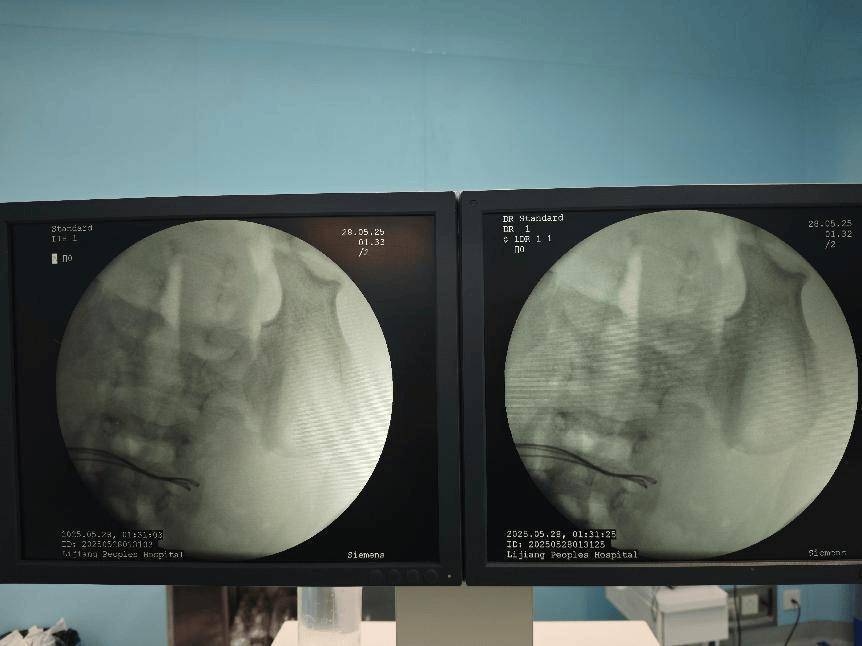

术中取出小肠异物

经过研判,医疗团队凭借着精湛的技术和坚定的信念,克服了重重困难,成功取出了该病人体内的37颗磁力珠,并对穿孔部位进行了细致的修补。经过数小时的紧张手术,通过腹腔镜、内的联合操作,让病人脱离了生命危险。

术中完善床旁DR见腹腔内已无异物